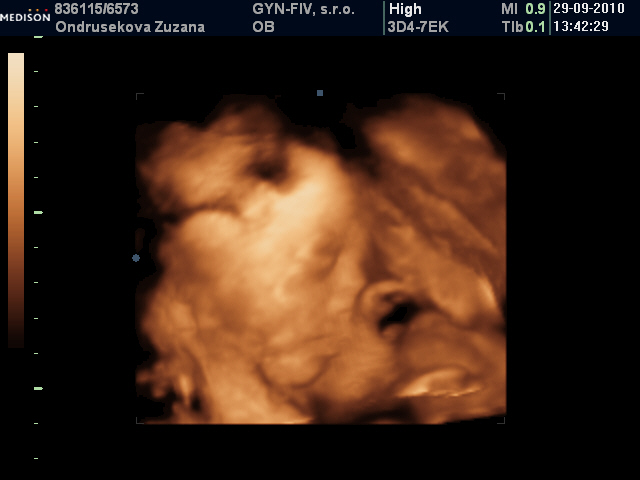

♥70 dní do porodu♥holčička má 1430 g a je hlavičkou dolů♥